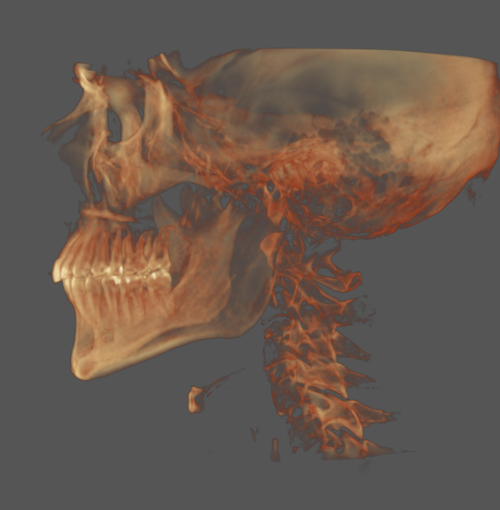

I'm currently 22 and have a recessed mandible, maxilla and narrow palate, all of these are not severe but add up, this has lead to mild sleep apnea, TMJ, and migraines.

I'm currently 22 and have a recessed mandible, maxilla and narrow palate, all of these are not severe but add up, this has lead to mild sleep apnea, TMJ, and migraines.